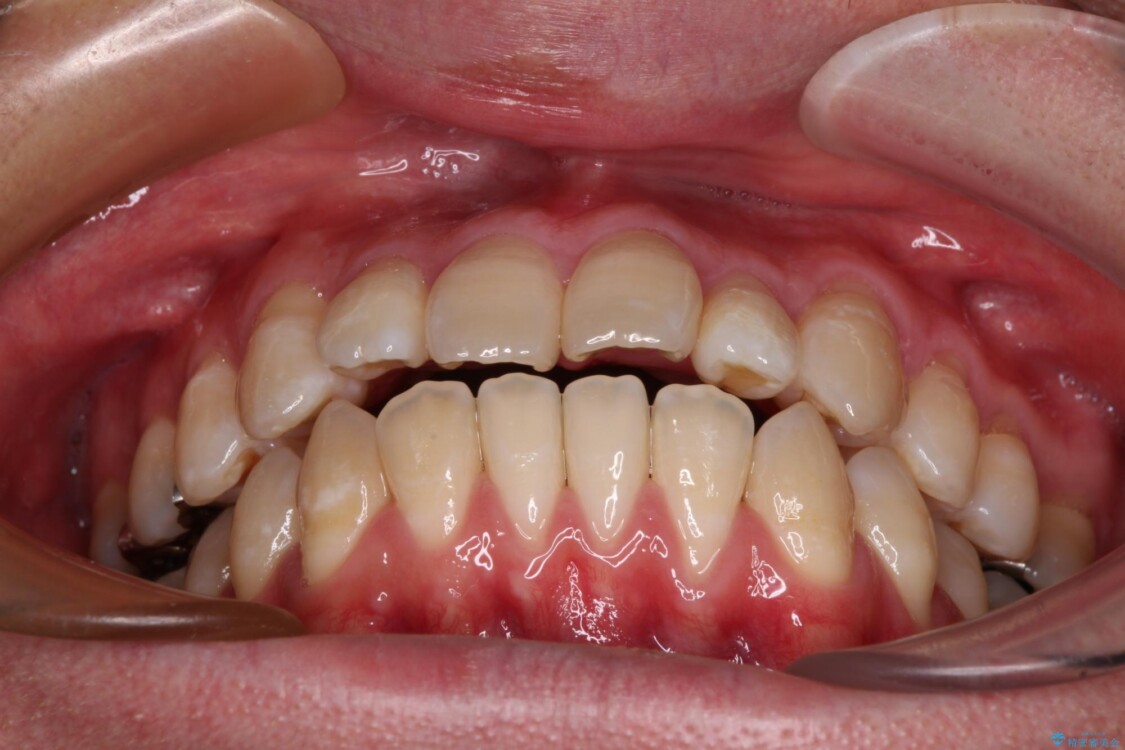

治療前

• 口元の突出感を改善!目立ちにくいワイヤー矯正で自信を持てる自然な横顔に 治療前画像

「横から見ると唇が前に出て見えるのが気になる…」 「マスクを外すのが恥ずかしい…」 そんな口元の突出感に悩まれてご来院された患者様。

精密検査の結果、上下左右の小臼歯4本を抜歯し、そのスペースに前歯を後方へ移動させる矯正治療をご提案しました。